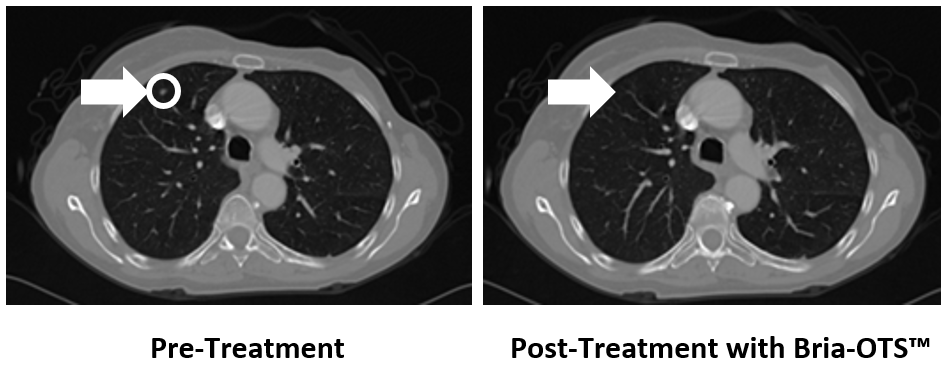

Figure 1: Treatment with Bria-OTS™ monotherapy resulted in 100% resolution of tumor in the lung of the MBC patient following 4 injection cycles[1]

As shown in Figure 1, the lesion in the patient’s right lung (left side of the image) is no longer detectable on the images taken 2 months after treatment with Bria-OTS™ monotherapy.

This 78-year-old woman with metastatic breast cancer (hormone receptor positive, HER2 negative) had failed several prior lines of therapy and received the lowest dose level in the Phase 1/2a Bria-OTS™ study. At enrollment on Nov 21, 2024, she had extensive metastases including multiple bone, lymph node and lung metastases. Following 4 injections with Bria-OTS™ every 2 weeks, the lung metastasis completely resolved, and she had stable disease elsewhere.

[1]Note that the other white dots in the lungs are blood vessels.